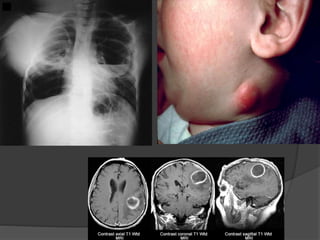

Which type ofPID is associated with this cartoon